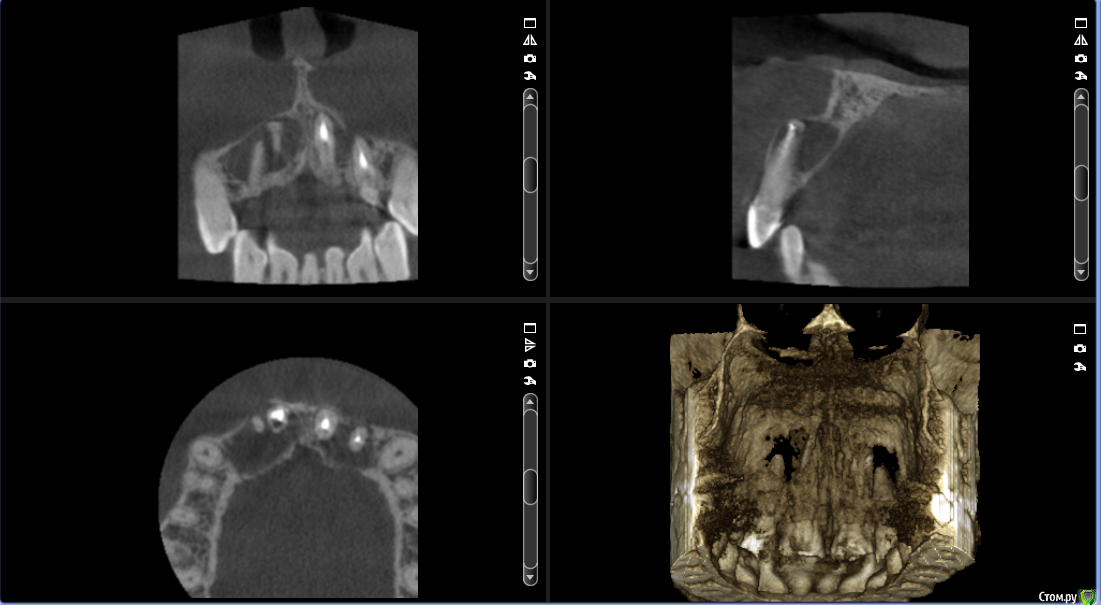

___49___ Опубликовано 5 декабря, 2016 Поделиться Опубликовано 5 декабря, 2016 Что скажите коллеги - интересно ваше мнение , советы. 11 зуб - канал разбит - пока не решил, что с ним делать. Остальные зубы однозначно хочу оставить + эндо 12 му. А после резекция..... Ссылка на комментарий

___49___ Опубликовано 5 декабря, 2016 Автор Поделиться Опубликовано 5 декабря, 2016 Пробуйте ортоградно. МТА в помощь...Опешите пожалуйста подробней как вы бы это выполнили ? я думаю - канал ортоградно перелечить в 11 , эндо в 12 и после резекцию с ретроградкой МТА. Ссылка на комментарий

Евгений Ходыкин Опубликовано 6 декабря, 2016 Поделиться Опубликовано 6 декабря, 2016 Опешите пожалуйста подробней как вы бы это выполнили ? я думаю - канал ортоградно перелечить в 11 , эндо в 12 и после резекцию с ретроградкой МТА.При таких "разбитых" апексах всё отмываете, апексифицируете МТА. Выше можно и гутту. Ничего по не резецировать. Сделайте КТ через год, там и оцениваете результат... Ссылка на комментарий

dent-a Опубликовано 6 декабря, 2016 Поделиться Опубликовано 6 декабря, 2016 Пробовал делать декомпрессию кисты, чтоб она инволютировала, и типа остеогенез преобладал , пол года и потом гораздо более мелкую убрать.Как было так и осталось...без претензий на оригинальность - ИМХОТут или эндо МТА или аналог, шина, резекция....оттянуть имплантациюИли под снос. 1 Ссылка на комментарий